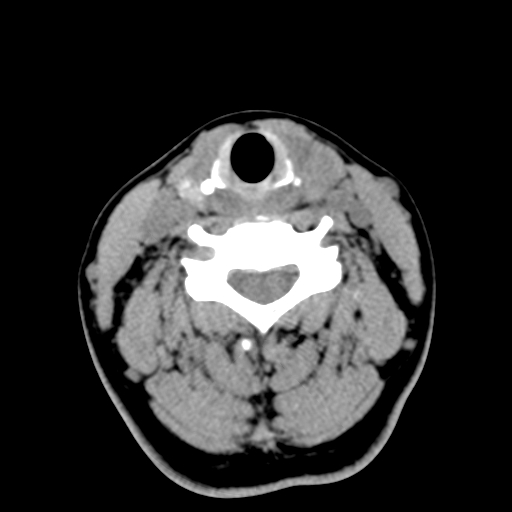

女,44岁,左颈部肿块伴疼痛两个月。患者不能做增强扫描。

左侧甲状腺明显肿大,密度不均匀性减低,正常之钙化基本消失,残留少许呈云雾状及颗粒状。其边缘不规则、不清晰,与前部联合处正常甲状腺不能分界不清,但尚可与周围其他组织分辨。颈动脉鞘区无明显淋巴结肿大。

多考虑:左侧甲状腺癌。

左侧甲状腺弥漫性肿大,密度减低,与气管及周围血管等分界清晰,颈部未见明显淋巴结肿大.首先考虑左侧甲状腺瘤;其次考虑甲状腺炎;不排除甲状腺癌可能.

多考虑甲壮腺腺瘤可能性大,周边的脂肪间隙显示尚清楚,未见明显肿大淋巴结.气管未见受压.